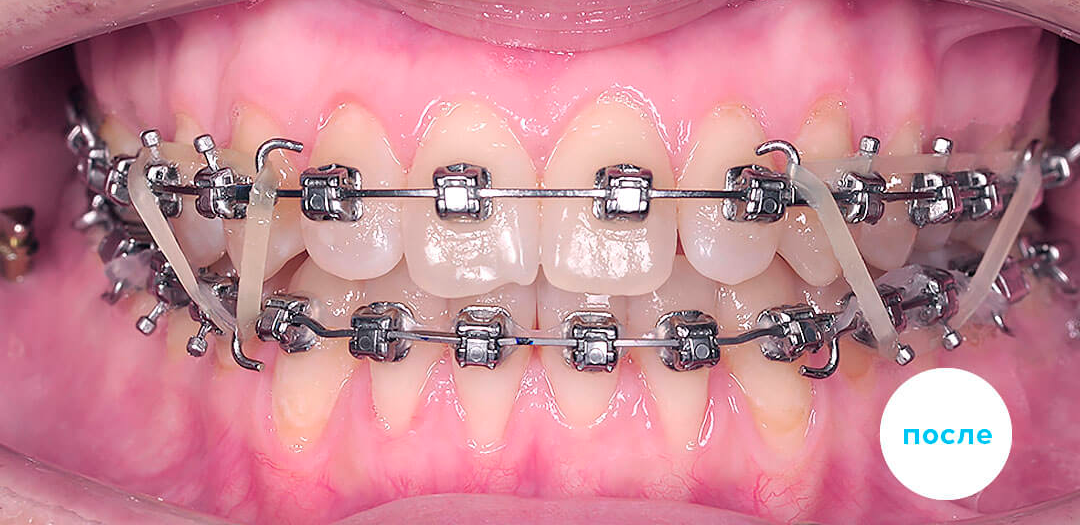

Проведено лечение перекрестного прикуса c использованием эластиков

Смотреть кейс